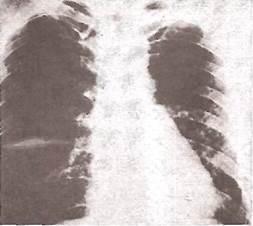

Выявлению малых количеств плеврального выпота (более 100-150 мл) помогает латерография

— рентгенологическое исследование в положении пациента на боку на стороне поражения (рис. 26). При наличии свободной неосумкованной жидкости появляется пристеночная узкая лентовидная тень (рис. 27).

Рис. 26.

Принцип методики латерографии.

Рис. 27.

Узкая полоска плеврального выпота, выявленная при латерографии